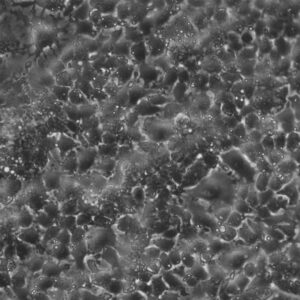

Morphology: Epithelial-like

Growth Properties: Adherent

Description: HuH7 was established in 1982 by Nakabayashi et al. from a 57-year-old Japanese male with well differentiated hepatocellular carcinoma.